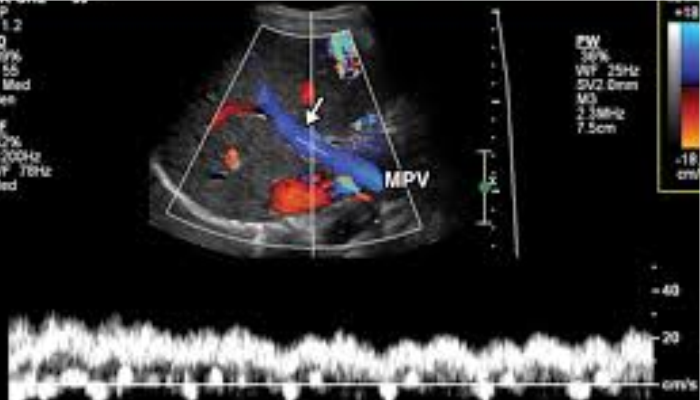

This specialized technique evaluates the movement of blood through your arteries and veins.

Renal Doppler: Examines blood flow to the kidneys.